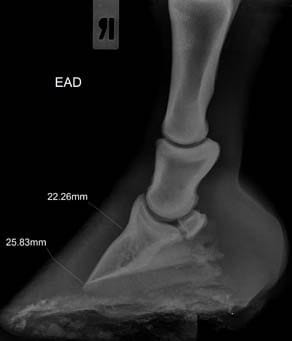

La radiología digital directa es una herramienta indispensable para el estudio v valoración en numerosas áreas de la atención veterinaria: valoración de cojeras, exámenes pre-compra, estudios radiológicos, diagnósticos más precisos en patologías, heridas, enfermedad…

Por eso nos mantenemos al día y nos renovamos con nuevos equipos de radiología digital directa que incorporan herramientas de diagnóstico y valoración con ventajas como:

- Herramientas de medidas más completas y potentes

- Medidas e imagen 3D para evaluación del pie equino

- Imagen hibrida. Diagnóstico v herrado